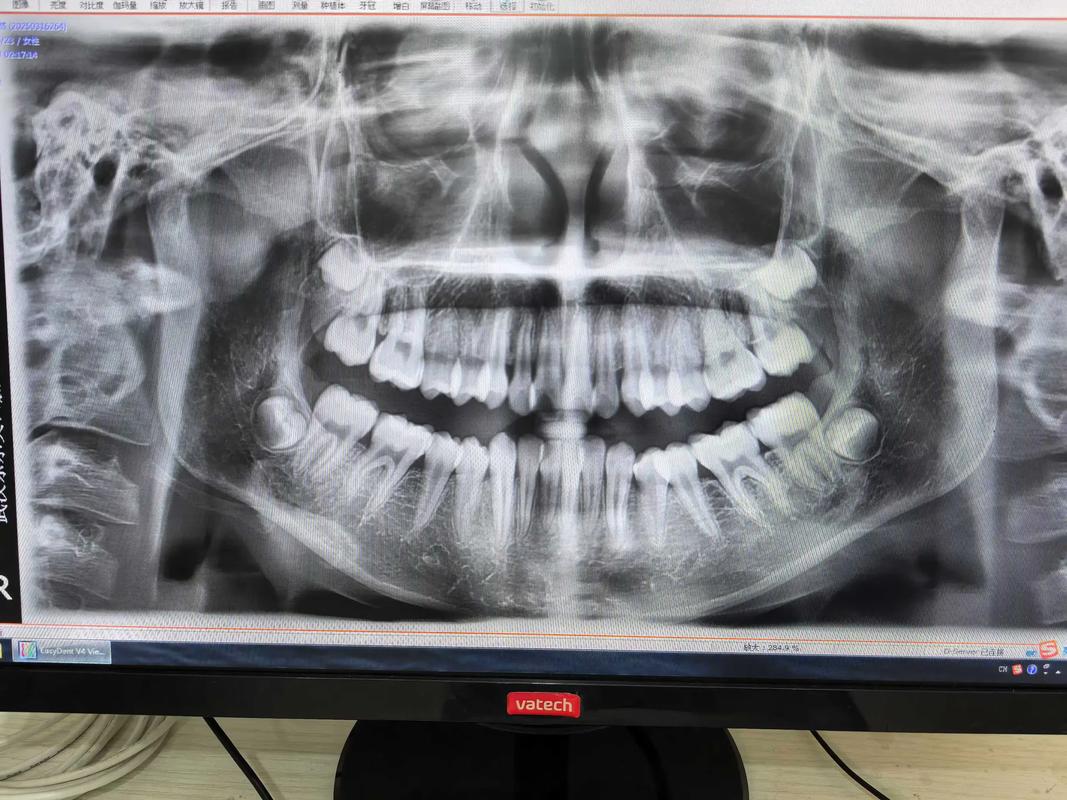

澳大利亚的正畸医疗体系以规范化和专业化著称,所有正畸医生均需经过严格的专科培训,通常需完成牙医学士学位后,再攻读3年全日制正畸硕士或博士学位,并通过国家执业资格考试,Dr T正是这一体系的践行者,其诊所配备先进的数字化设备,如iTero口内扫描仪、3D打印技术及CBCT影像系统,能够在治疗前精准模拟牙齿移动路径,预测矫正效果,大幅提升治疗精准度与患者体验。

在治疗过程中,Dr T强调“医患协作”,每次复诊都会详细解释牙齿移动进度,并根据患者反馈调整方案,一位成人患者因牙齿拥挤及“地包天”问题寻求矫正,Dr T通过CBCT分析发现其存在轻度颌骨发育异常,结合患者“不希望影响社交形象”的需求,最终采用隐形矫正配合微种植体支抗,既解决了牙齿排列问题,又避免了传统矫正可能带来的面部外观改变,治疗结束后患者不仅牙齿整齐,咬合功能也得到显著改善。